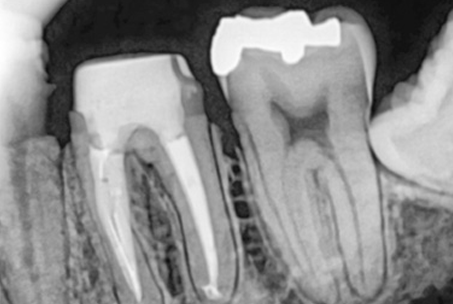

위 사진들은 현직 치과의사들이

저희 웃는얼굴 치과에서 치료 받은 실제 사례들입니다.

비 전문가 눈에는 그냥 흔한 엑스레이 사진일 뿐이겠지만

치과의사들이라면 알아챕니다.

저 치료가 얼마나 난이도 있는 치료였는지,

얼마나 정성이 들어갔는지를 말이지요.

크라운과 기존의 신경관 충전물질을 제거 후

다시 신경치료를 진행하는 술식입니다.

일반적인 신경치료보다 어렵고 성공률이 떨어지기 때문에

전문적인 치료가 필요합니다.

특히 신경관이 막혀있거나 신경관에 POST가 박혀있는 경우

재신경 치료의 난이도는

매우 높아지며, 많은 환자분들이

재신경치료가 불가능하다며 발치를 권유 받습니다.

하지만 웃는얼굴치과에서는 특수 초음파 기구로 막힌

신경관을 찾거나

신경관에 박혀있는 POST를 제거한 후

재신경치료를 하여

환자분들의 치아를 살려드리고 있습니다.